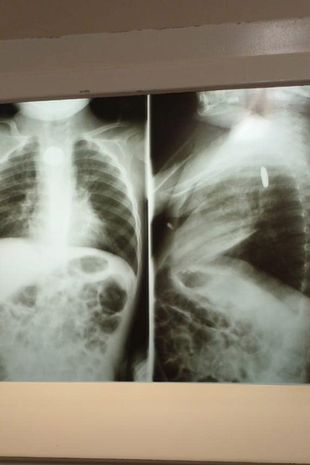

Lekarze prześwietlili chłopca

Lekarze prześwietlili chłopca © Facebook

Okazało się, że w przełyku chłopca utknęła bateria. Niestety, by ją wyciągnąć, konieczne było przeprowadzenie natychmiastowej operacji, a szpital nie był przygotowany na taki zabieg. Dylan został przetransportowany do większego ośrodka w Hermosillo.

Ze względu na zatkane drogi oddechowe, chłopiec długo był niedotleniony. Dlatego też przed rozpoczęciem operacji lekarze musieli go natlenić, by jego stan się ustabilizował. W tym czasie bateria eksplodowała w przełyku, co doprowadziło do pogorszenia jego stanu.